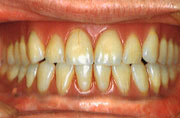

●患者:74歳・男性

●主訴:下顎総義歯床下粘膜の疼痛/下顎にOIBが装着され安定しているのに対して可撤性である上顎義歯に不満を訴える。

| 初診時 | 下顎に適用されたOIB及び上顎総義歯 |